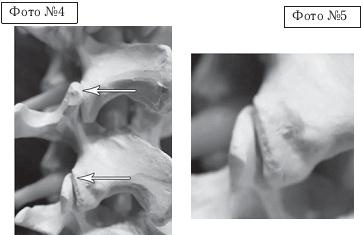

Как вы помните, позвоночно-двигательный сегмент является структурой трёхопорной (межпозвонковый диск и два дугоотростчатых сустава, на которые приходится вся нагрузка от веса вышележащей части тела и мышечных усилий). Чтобы понять суть данного метода, для начала рассмотрим на макете позвоночника, что происходит в процессе вытяжения с межпозвонковым сегментом.

На фото № 4 макета позвоночника наблюдается нормальное взаимоотношение суставных поверхностей в дугоотростчатых суставах.

На фото № 5 — нормальное взаимоотношение суставных поверхностей в дугоотростчатом суставе (увеличенный вариант).